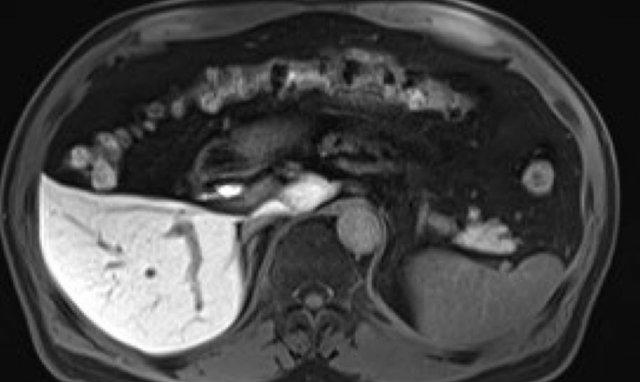

Washout – Vỏ bao

Đây là một bệnh nhân khác với tổn thương có ngấm thuốc và hiện tượng washout.

Lưu ý vỏ bao ngấm thuốc trên thì muộn.

Vỏ bao là một trong những đặc điểm chính của HCC và có thể hoàn toàn hoặc một phần.

Vỏ bao cần được tính vào trong phép đo kích thước của tổn thương.